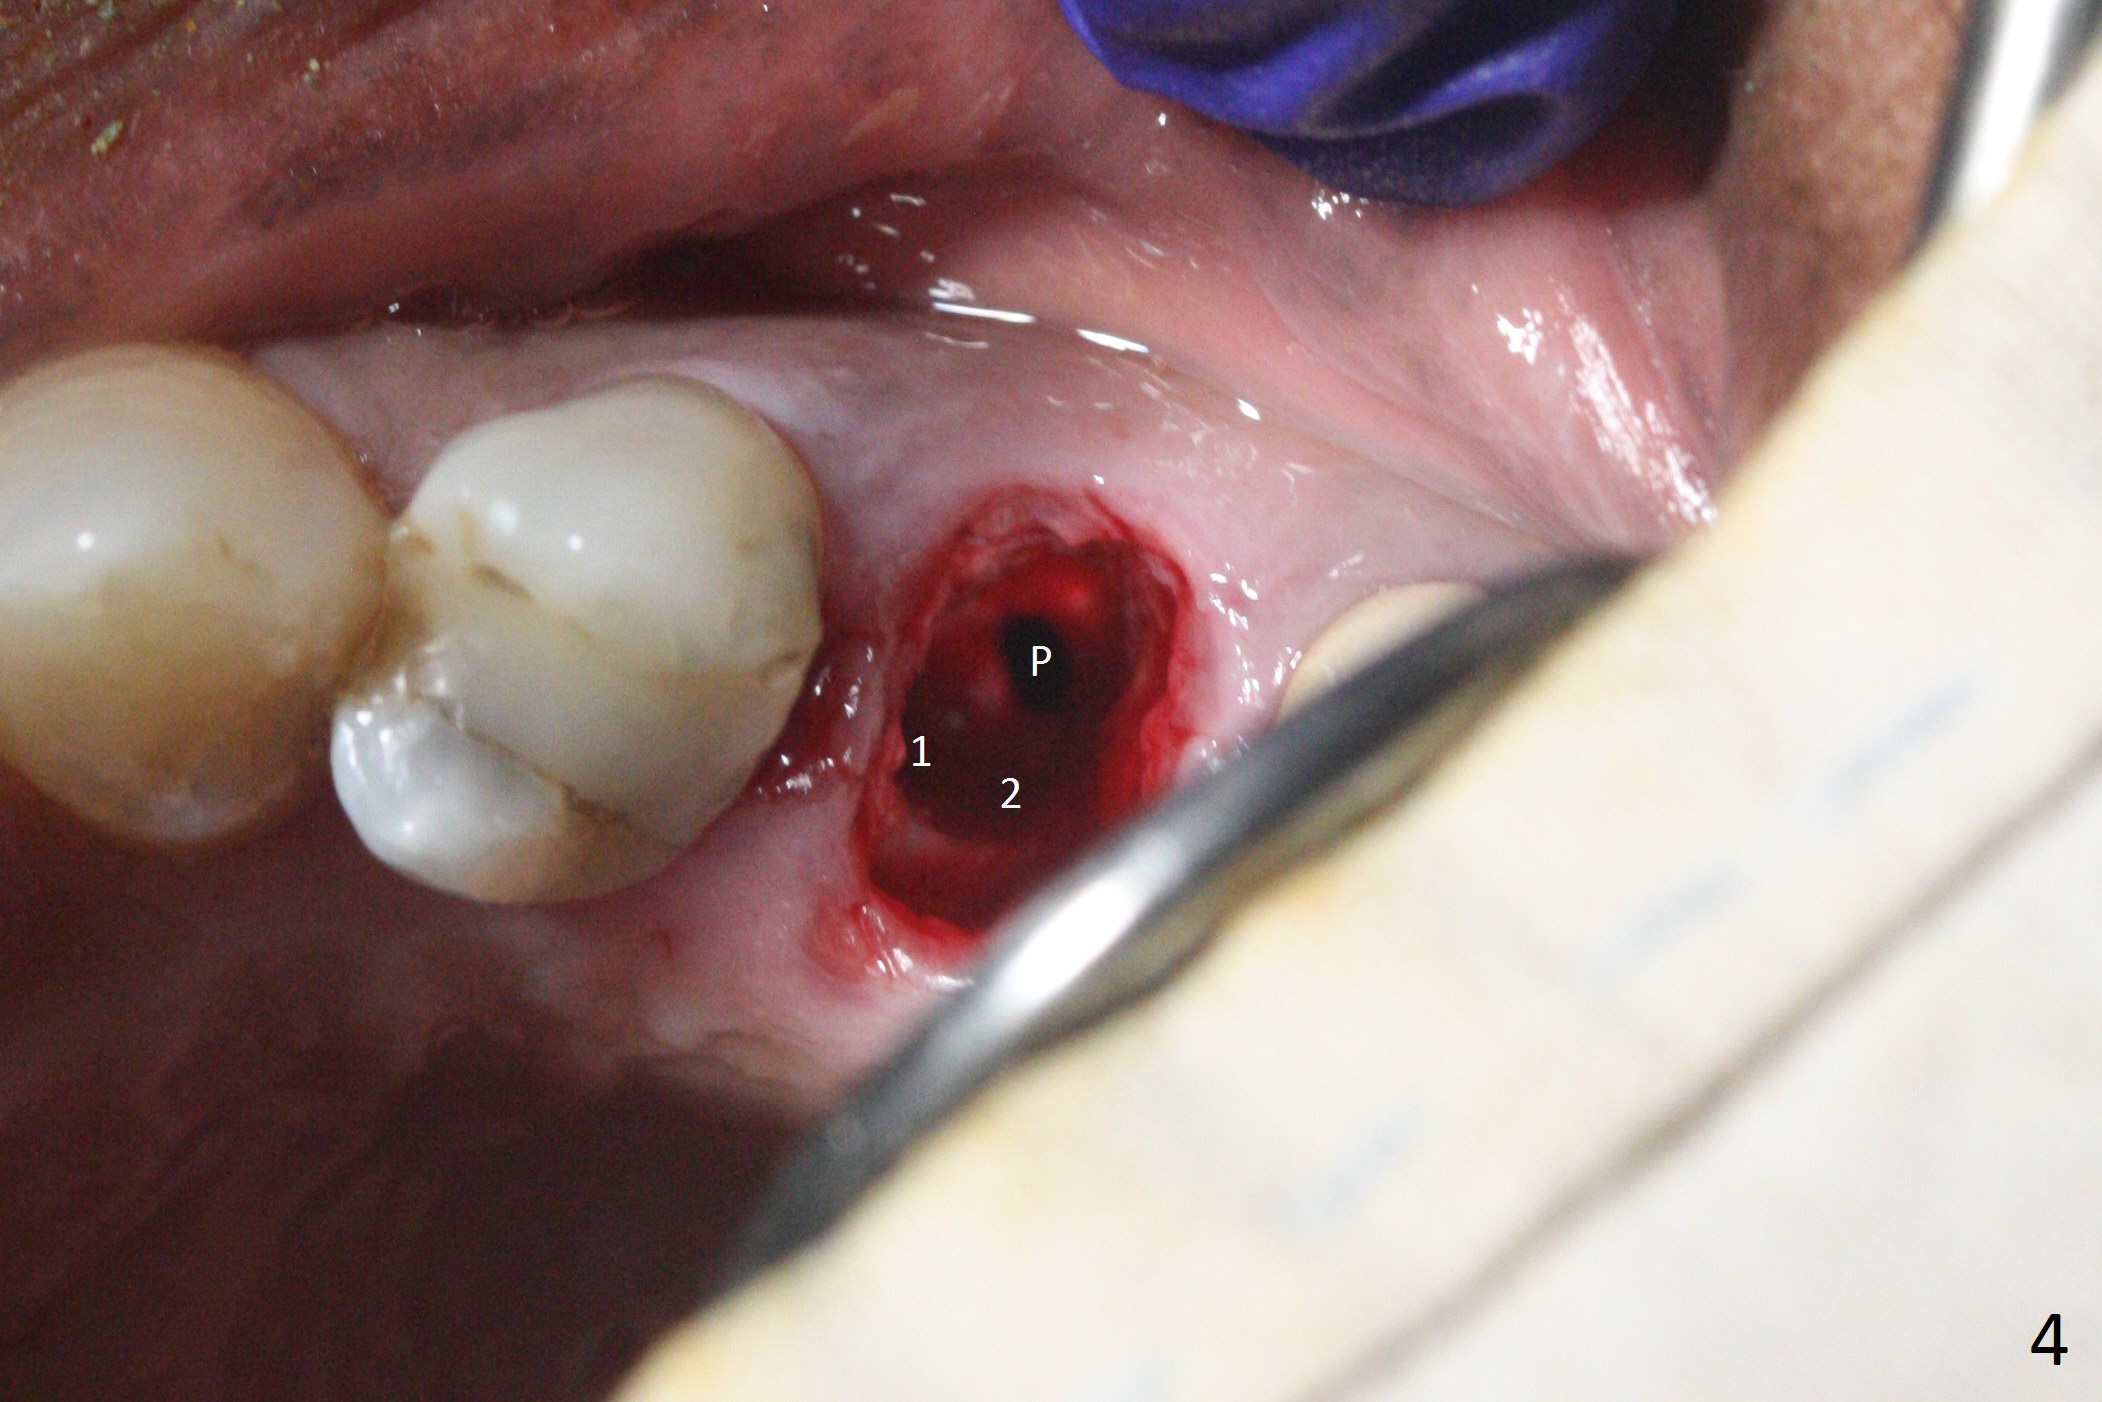

Since the apical native bone is limited at #13 after extraction, no PA is taken until a 4x11 mm dummy implant is placed after 1.6 mm and 3.3 mm drills for 13 mm (Fig.1). After using Lindamann bur to move the osteotomy distal and reusing 3.3 mm drill, the trajectory of a 4.5x11 mm IBS dummy implant improves (Fig.2,3 with low stability). When the implant is removed, the buccal portion of the socket is found to be perforated (Fig.4 P). Although the reason for the perforation is unknown, it is repaired by insertion of a piece of PRF plug, followed by allograft. #1 and 2 in Fig.4 represent the 1st and 2nd osteotomies, as shown in Fig.1 and 2, respectively. The trajectory of the final 5x13 mm implant is acceptable (Fig.5-7, different angulations), so is insertion torque (45 Ncm). After placing a 5.5x4(4) mm abutment, an immediate provisional is fabricated (Fig.8 P) with occlusal clearance (*). The interdental papillae remain in place 12 days postop (Fig.9 *). There is no sign of postop sinus infection. The provisional is loose 18 days postop; the abutment is changed to 5x4(3) mm (Fig.10). It is difficult to catch the mesial margin of the abutment for impression 4 months postop, due to poor oral hygiene and the short cuff (3 mm, Fig.11). The appointment for impression is rescheduled with emphasis on oral hygiene and no wearing the provisional for a few days prior to next appointment. Bone has grown into the space between the 1st and 2nd threads 5 months post cementation (Fig.12) and the bone is normal, solid and dense 2 years 11 months post cementation (Fig.13 >). There is mesial open margin of the tooth #14 (Fig.13,14 *).